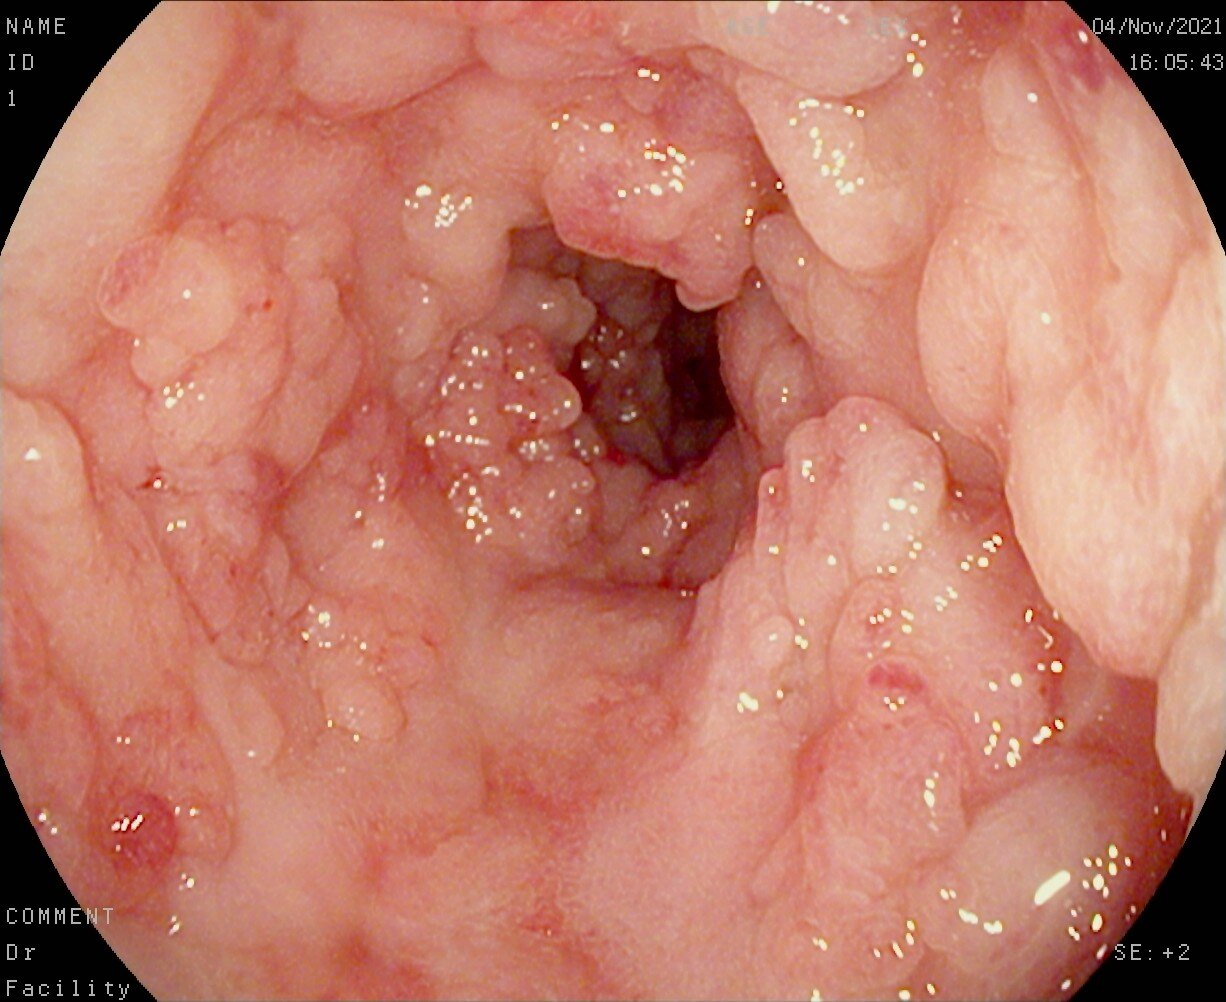

这幅图,不是简单的医学图解,而是我生活中的每一个细节。它描绘了那些无休止的腹痛、腹泻,还有那些因为营养不良而日渐消瘦的日子。每一次去医院,看着那些冰冷的仪器和面无表情的医生,我的心就像是被重重地敲打了一下。